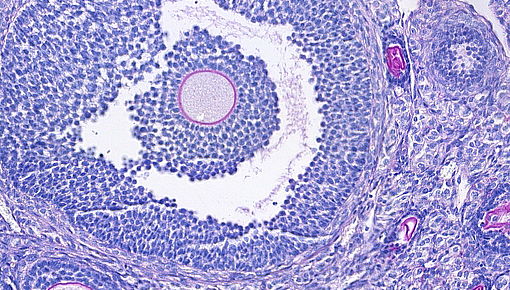

Entscheidene Meilensteine der Eierstockentwicklung finden beim Menschen pränatal und bei Mäusen perinatal statt, wie z. B. die Bildung des weiblichen Keimzellenpools. Die Keimzellen und die sie umgebenden spezialisierten Stromazellen bilden die Follikel, die für den Eisprung verantwortlich sind und eine Hauptquelle für Sexualhormone während des weiblichen Fortpflanzungslebens darstellen. Wichtig ist, dass fein abgestimmte Immunreaktionen die normale Follikulogenese, den Eisprung und die Bildung und Rückbildung des Gelbkörpers entscheidend unterstützen. So regulieren Makrophagen in den Eierstöcken diskrete Umbau- und Gefäßbildungsprozesse, die den Zugang der Follikel zu Nährstoffen und Steroidsubstraten und den Austritt von Hormonen in den Blutkreislauf sicherstellen.